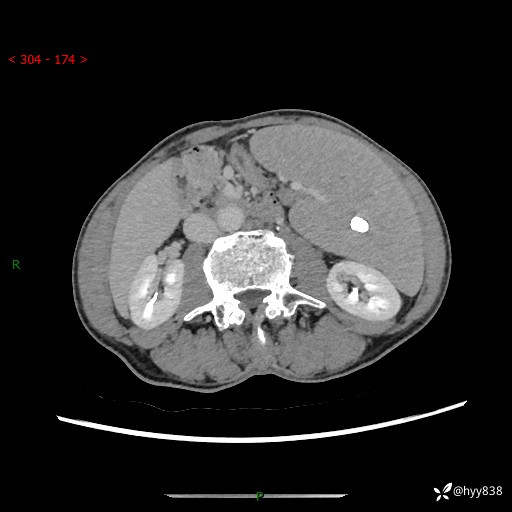

老年男性,脾大并脾脏弥漫粟粒状低密度,淋巴瘤 VS 肉芽肿 VS 血管瘤---结果公布

简要病史: 患者于3月前无明显诱因出现脾大,伴腹部轻微不适,具体不详,无腹痛、腹泻、腹胀,无头晕、头痛、乏力,无恶心、呕吐、呕血,无胸闷、气短、胸痛不适

上腹部CT平扫+增强